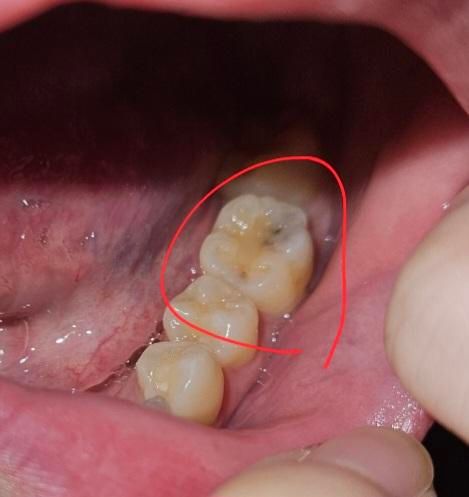

사진처럼 보이는 치아는 중지된 충치일 수 있나요?

이쑤시개로 쑤셔봤는데 아프지도 않고 긁히지도 않아요.. 진행중인 충치라면 어떤 치료를 받는게 제일 자연치아를 안건드릴수있나요?

• 2번 째 사진

위쪽부터 충치가 진행되면서 안쪽까지 썩게되는겁니다. 위에서는 충치가 작아보여도 실제로 안쪽은 충치가 넓은 경우가 많습니다.

1. 작은 열구에서 진행되어 안쪽에서 충치가 커지기도 합니다.

3. 엑스레이를 찍어보고 충치의 깊이를 알아야겠으나 사진상 저런 진행정도면 일반적으로 레진으로 떼워주면 될 것 같습니다.

충치가 치아 표면의 틈, 특히 치아 사이나 교합면의 작은 균열로 침투하여 내부에서 상아질을 침식할 수 있습니다. 사진에서 보이는 치아가 검게 변색되었다면, 그것이 이미 진행이 멈춘 중지된 충치이거나 진행초기일 가능성이 있습니다.

치아 내부 충치는 엑스레이나 정밀 검사를 통해 확인해야만 정확한 진단이 가능하기에 보다 정확한 상태 확인을 위해 치과 진료를 권합니다.